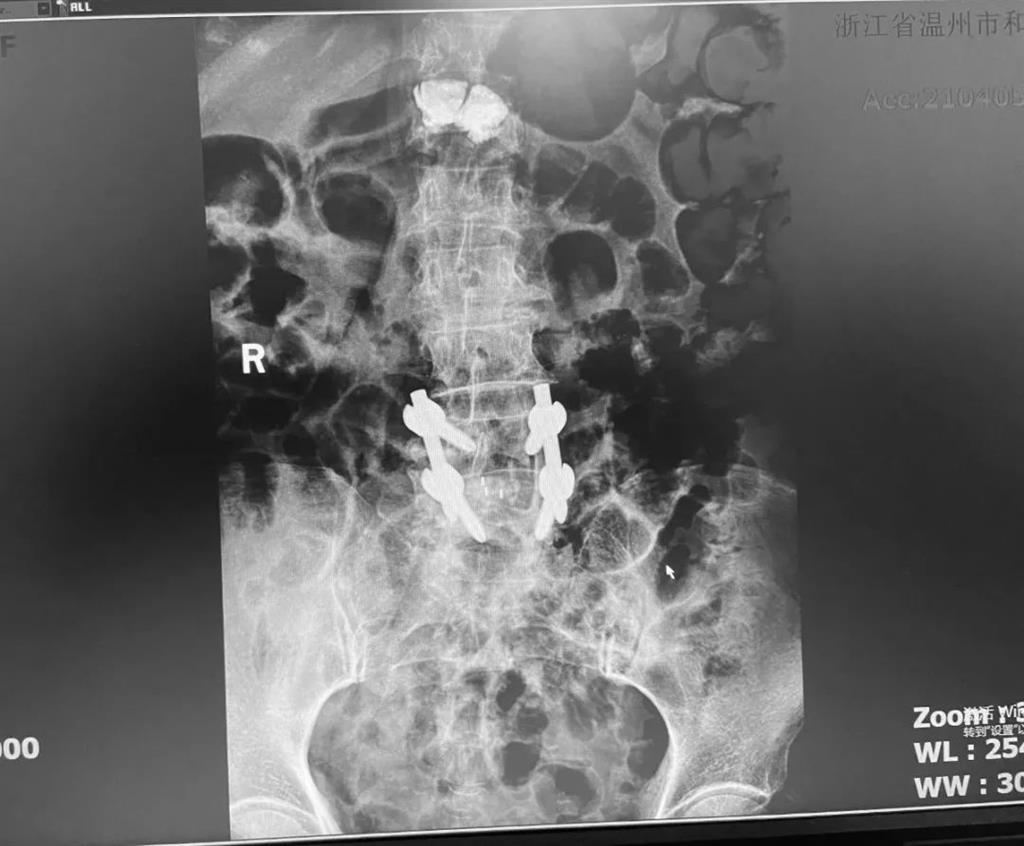

據(jù)了解,脊柱內(nèi)鏡下腰椎融合術(shù)只需要打幾個(gè)“鑰匙孔”即可完成。聽起來是不是很簡單?在脊柱內(nèi)鏡下,劉丹主任先后為患者進(jìn)行了椎管減壓、椎間盤摘除,再實(shí)施椎弓根螺釘放置、椎體植骨融合內(nèi)固定,一系列步驟有條不紊。

看似簡單的幾個(gè)步驟,但實(shí)際上很復(fù)雜,需要主刀醫(yī)生有豐富的手術(shù)經(jīng)驗(yàn)和細(xì)致耐心的操作。

術(shù)中只需切開4個(gè)如“鑰匙孔”般大小的孔道